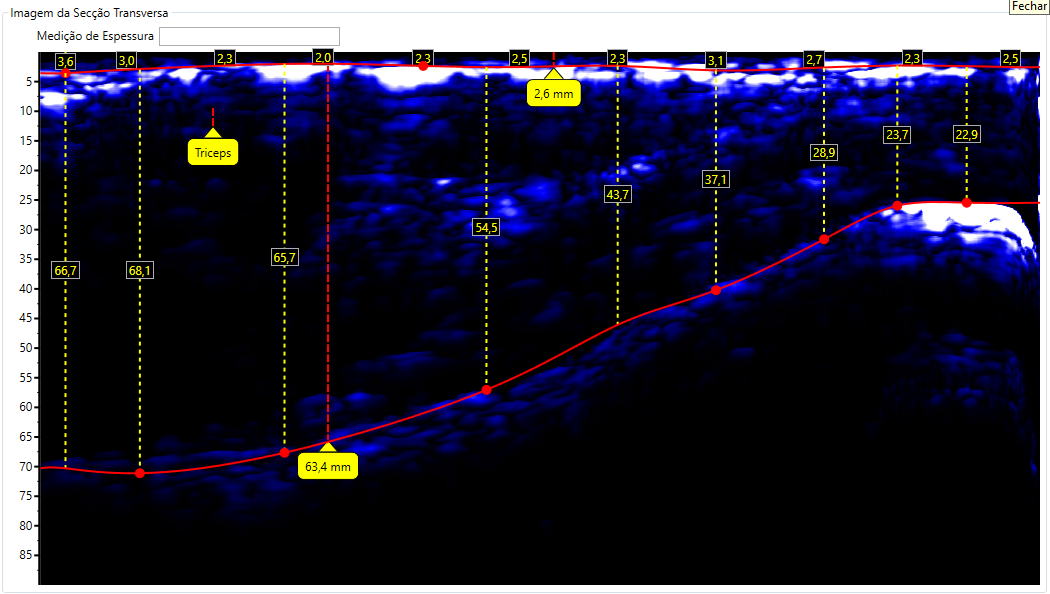

Escaneamento de Tríceps